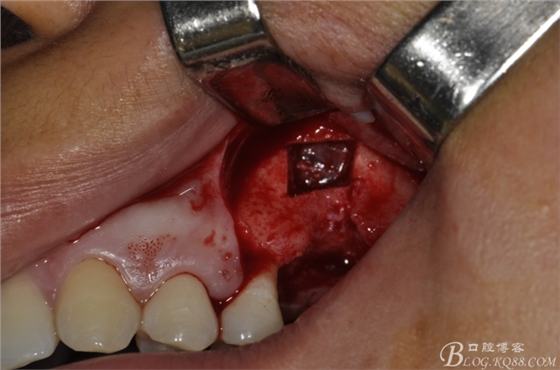

術(shù)中照片。

超聲骨刀切開(kāi)骨外板